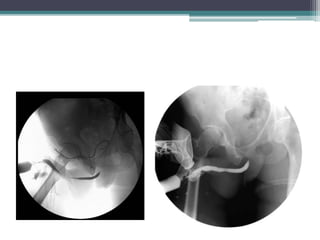

Case #3

โ€ข 67 M with long history of LUTS

โ–ซ On flomax/finasteride without improvement

โ–ซ Cystoscopy โ€“ urethral stricture

RUG